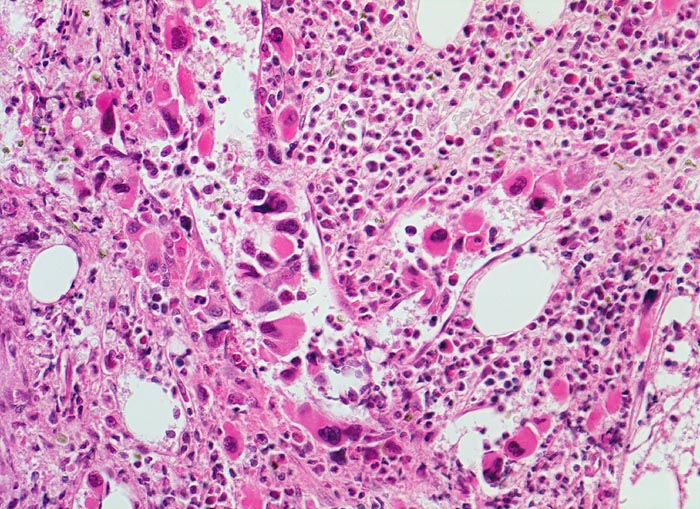

Primäre Myelofibrose (PMF)

Knochenmark, Beckenkamm

Vermehrung von atypischen, in Gruppen liegenden Megakaryozyten mit hypolobierten Kernen. Teils nacktkernige Megakaryozyten (d.h. praktisch ohne Zytoplasma). Die Megakaryozyten liegen in einem dilatierten Sinusoid bzw. unmittelbar daneben. Hyperplasie von ausreifenden Granulozyten. Erythropoese hypoplastisch. Durch die Fibrose entsteht der Eindruck von strömenden Zellen (links im Bild).

Splenomegalie, leichte Anämie, Leukozytose und Thrombozytose festgestellt bei einer Routineuntersuchung bei abgesehen von leichter Müdigkeit asymptomatischer Patientin.